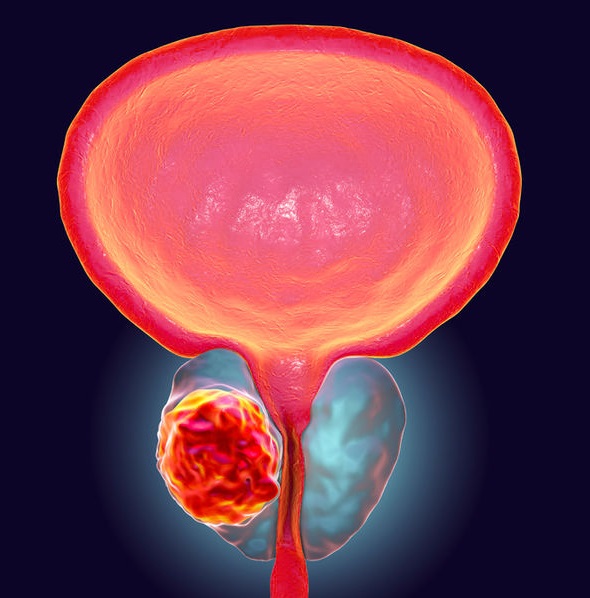

Prostate Cancer Illustration Stock Illustration – Illustration of …

Prostate Cancer – Stock Image – F031/9938 – Science Photo Library

Prostate Cancer – Stock Image – M865/0329 – Science Photo Library